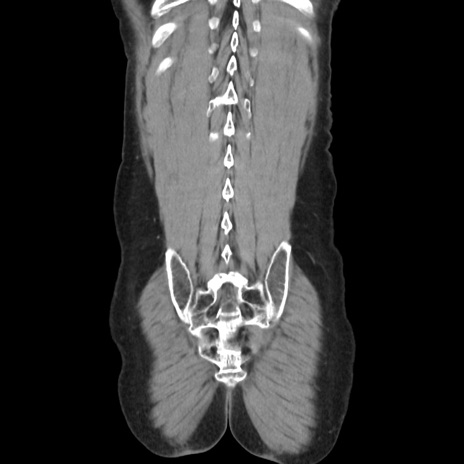

横断像